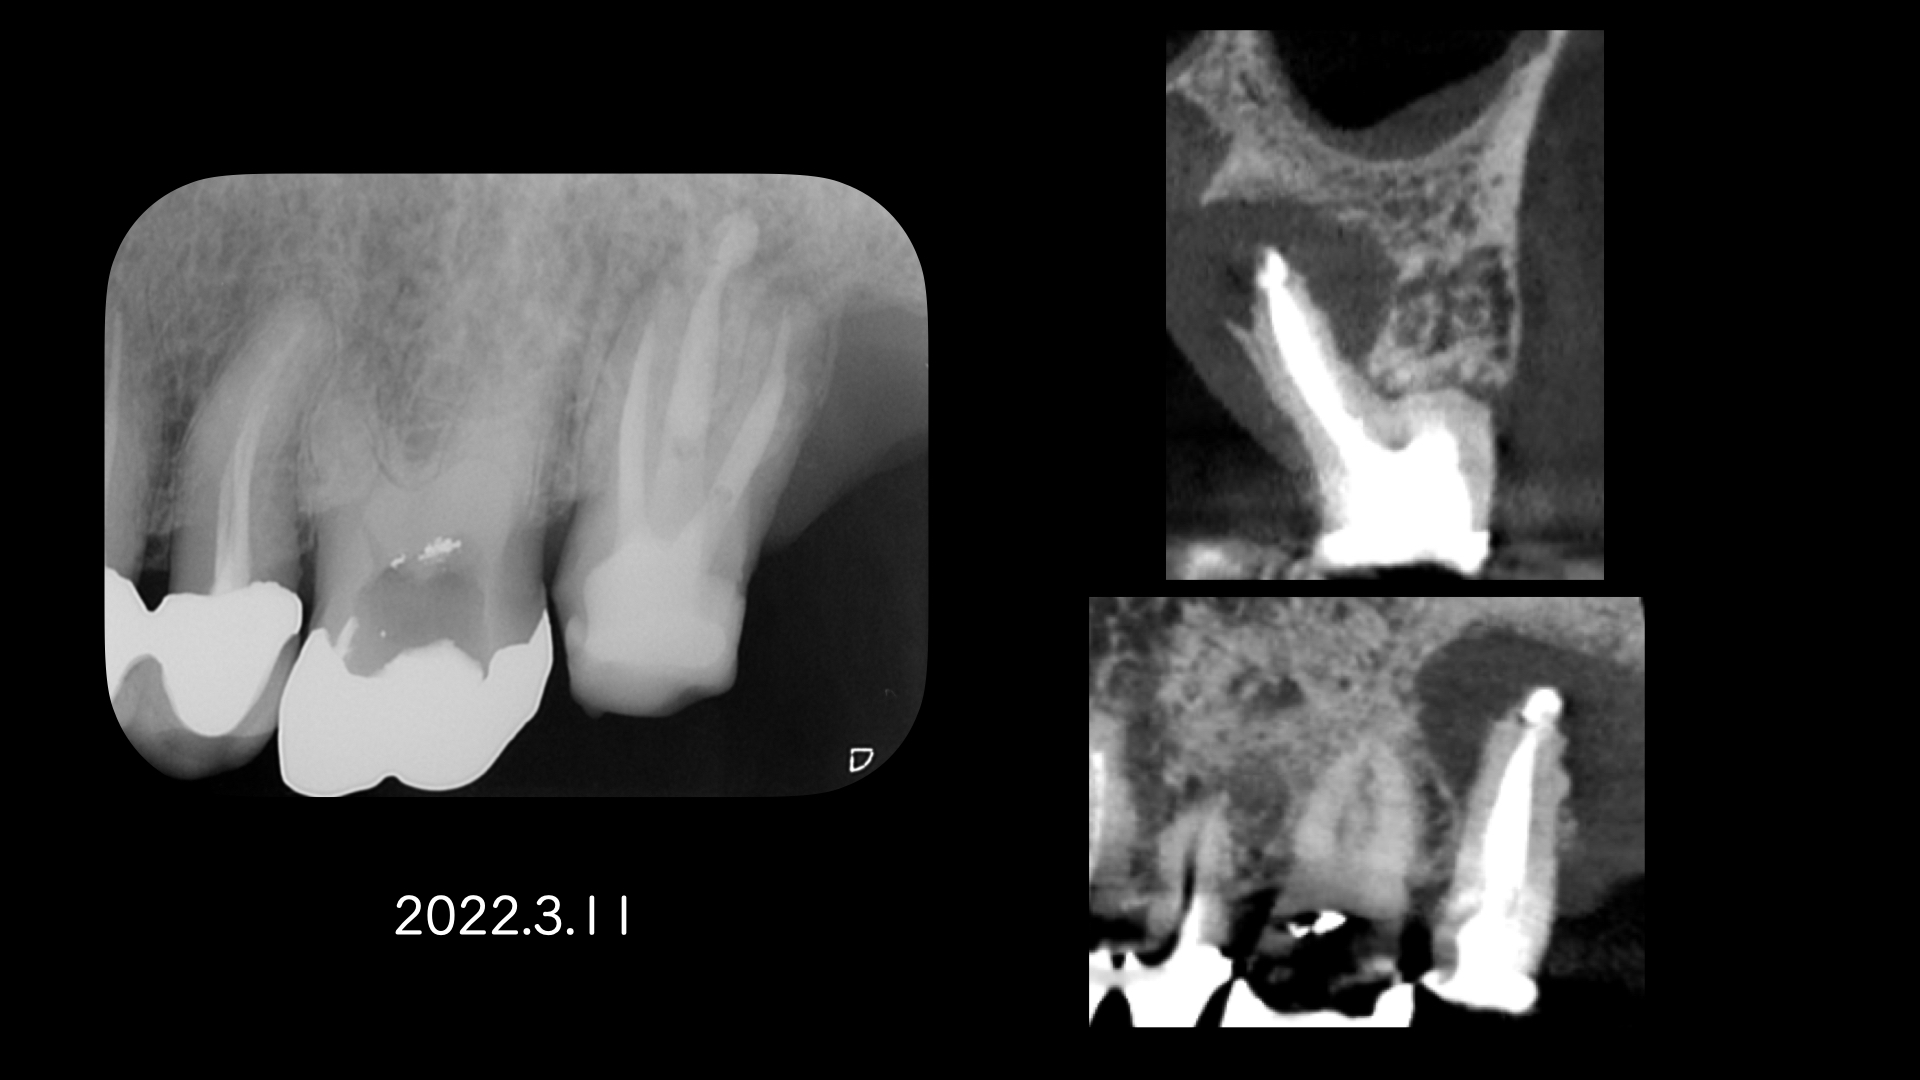

右の画像のCT上で根尖部にかなり大きな透過像があります。

根管治療はマイクロスコープを使用し、根管内は綺麗になった。と判断したので2回でMTAセメントにより根管充填をおこないました。

患者さんの都合もあり1年後に歯根端切除(外科的歯内療法)をおこなうことになりました。